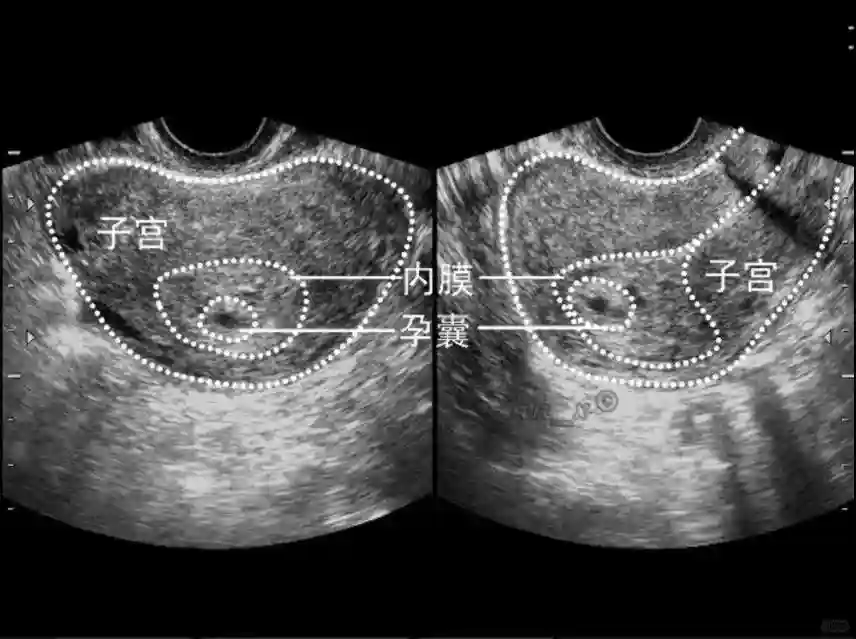

1??妊娠囊:早期妊娠囊:正常妊娠囊位于宫腔上段,表现为宫腔内圆形或椭圆形的无回声区,周边为完整的、厚度均匀的强回声环,强回声环厚度≥2mm,强回声是妊娠绒毛的回声,随着妊娠囊的增大,形成特征性的“双环征” ,10周以后消失。正常的妊娠囊增长速度是平均 1 mm /d。